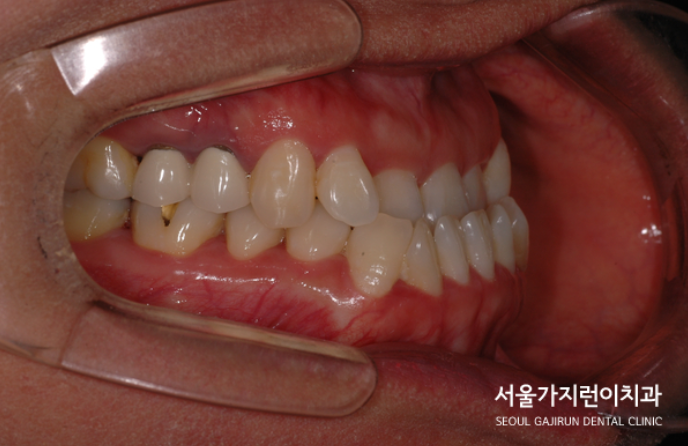

그래서 서울가지런이치과 교정과 의원에서는 치아를 발치한 후에 상하악 치아배열을 바로 잡기로 했는데요. 어금니 교합을 정상으로 만들기 위해서는 상당히 많은 치아 이동이 필요한 상태였습니다. 치아이동에 사용된 장치로는 전방 이동을 위한 미니스크류와 레버암이 있는데요. 치아를 이동시키면서 다른 치아가 움직이지 않도록 지지대 역할도 하면서 충분한 이동에 도움이 될 수 있도록 레버암까지 동원해 힘의 작용방향과 크기를 조절하였습니다.

주걱턱도 개선해야 했지만 정상교합으로 돌려놓기가 쉽지 않았는데요. 환자분의 경우 치료 1년 후 안정적으로 교정치료를 마쳤으며 6년이 지난 지금까지 안정적인 상태를 유지하고 있었습니다. 이 사진을 보면 교정이 잘 이루어져 재발하지 않았다는 것을 확인할 수 있는데요.